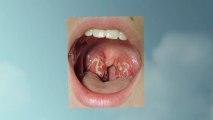

Tonsil Stones Treatment

http://beattonsilstones.bonuscb.com - Tonsil Stones Treatment